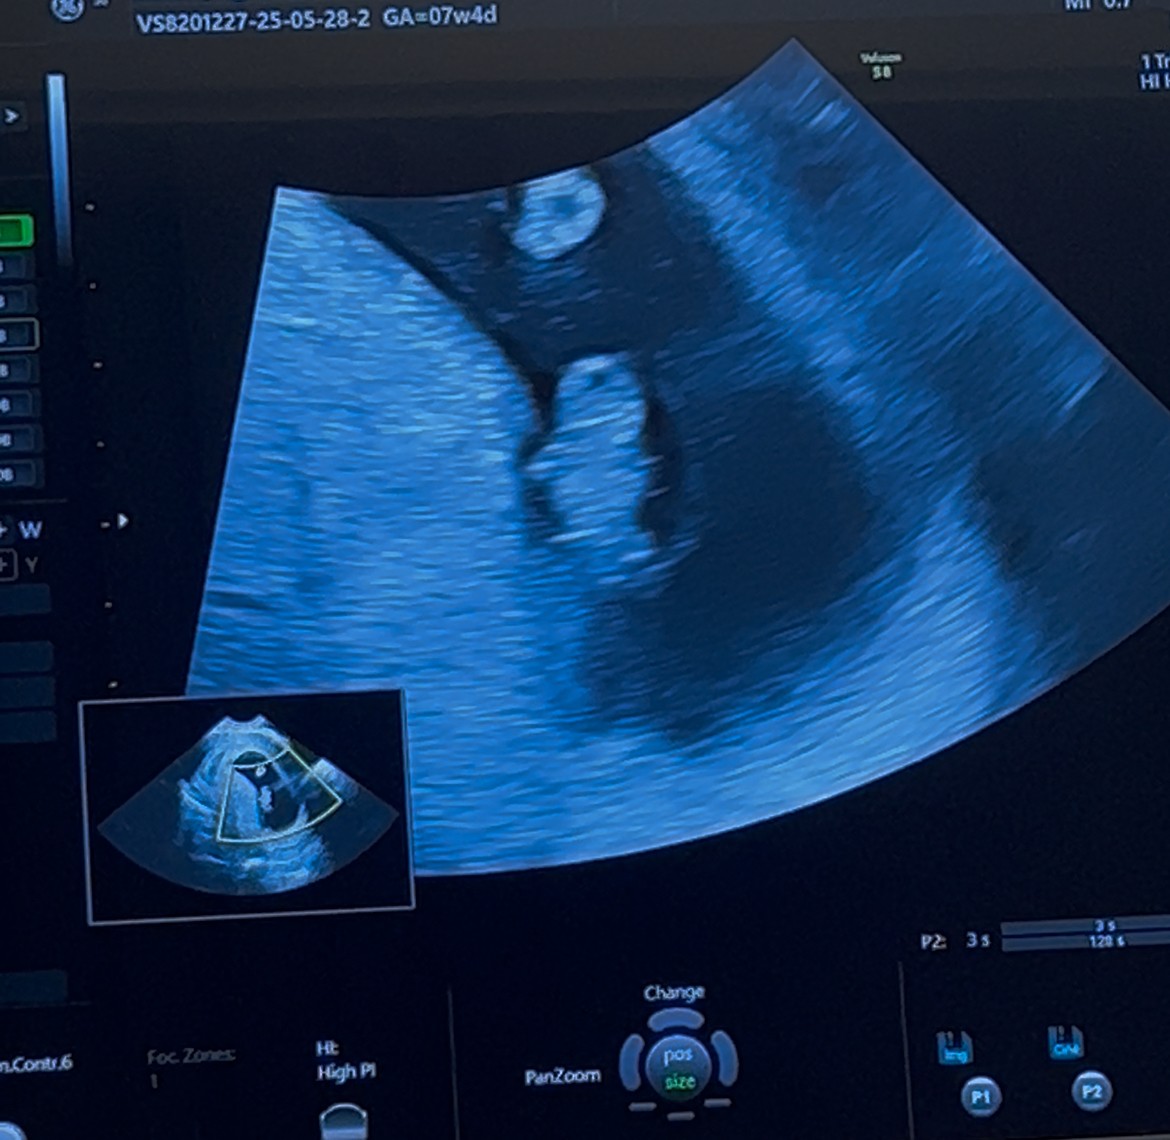

Ja się zastanawiam.Zobacz załącznik 1705399Termin zmieniony z 9 na 10 stycznia. Pani doktor nalega na badania nifty, któraś planuje je zrobić? Wzięłam już l4 do końca ciąży, nie ma ludzi niezastąpionych